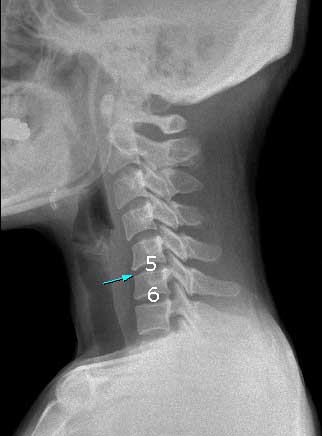

ֽ ȳϼ.. ũ ħ̶ ġϰ ִ ε ʾƼ ϴ Ա 帳ϴ. մϴ. 5~6 ̰ ڷ Ǿִ ȲԴϴ. ħ ڰ Ŵ µ ιڱ ִ ʰ Ȳġ ° ʰ ֽϴ. ȿ ʾƼ ۾ °Ͱ ſ °͵ .. ߶ µ ᵵ ̷ ô̰ ֽϴ. ʹ ļ ٸ ִ Դϴ.. غ..... ѹ Ȯغð Ѱ 亯 Ź帮ڽϴ. κμƮ Խô 20% Ͻô ٸ ᵵ ǵ帳ϴ. ȮϽð 亯ֽø ȭ 帮ڽϴ... ---ȸԳ-------- 1C~7C شǴ () ºҷ Ÿ ֽϴ. 3C., 5C.6C.ڰ հ ̳ 6C.ڸ , 6C. κ Ḳ , 6C.ھ Ḳ , 6C.ڻ , ()ũ( ߰Ż), ڸ(߹), ǥغ Ͻô Ͽ ߰ մϴ. ũ(߰Ż)ġ, հ , ġ, , Ḳ ġ ͳ õ ̻ 5-6 ִ ̰ ڸ ɴϴ. ѹ ġḦ ް ִ Ȳ̰ , ιڱʿ ϰ ִ Դϴ. ߶ а ̰ Ͼϸ ϰ ļ Ӹ ⳪ ġ ̵ϴ. ü ϴ.. Ϸ ϴ ȸ а ߾ ȸؼ Ϸ մϴ. ־ ۼ ϱ ƴϰ Ȱ ڽϴ. Ź帳ϴ. |